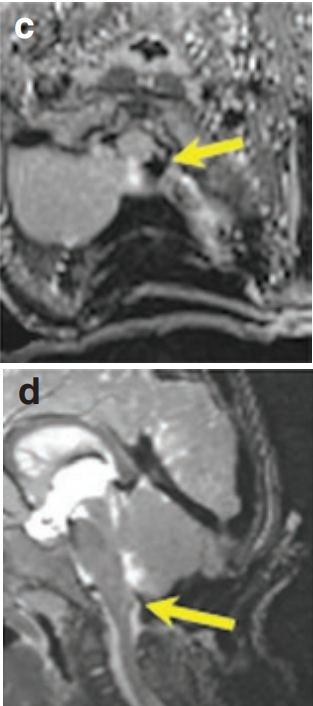

术中T1和T2MR(图c和d)显示肿瘤获得全切,无任何肿瘤残余。

通过枕后正中开颅术,暴露肿瘤。使用CUSA刀切除肿瘤,于左侧延髓外侧隐窝处发现肿瘤与后组颅神经根粘连,术中小心地将肿瘤与颅神经成功分离,颅神经成功保留,主要在处理后组颅神经时非常小心,保护吞咽功能。第九、十、十一颅神经保护得很好了。